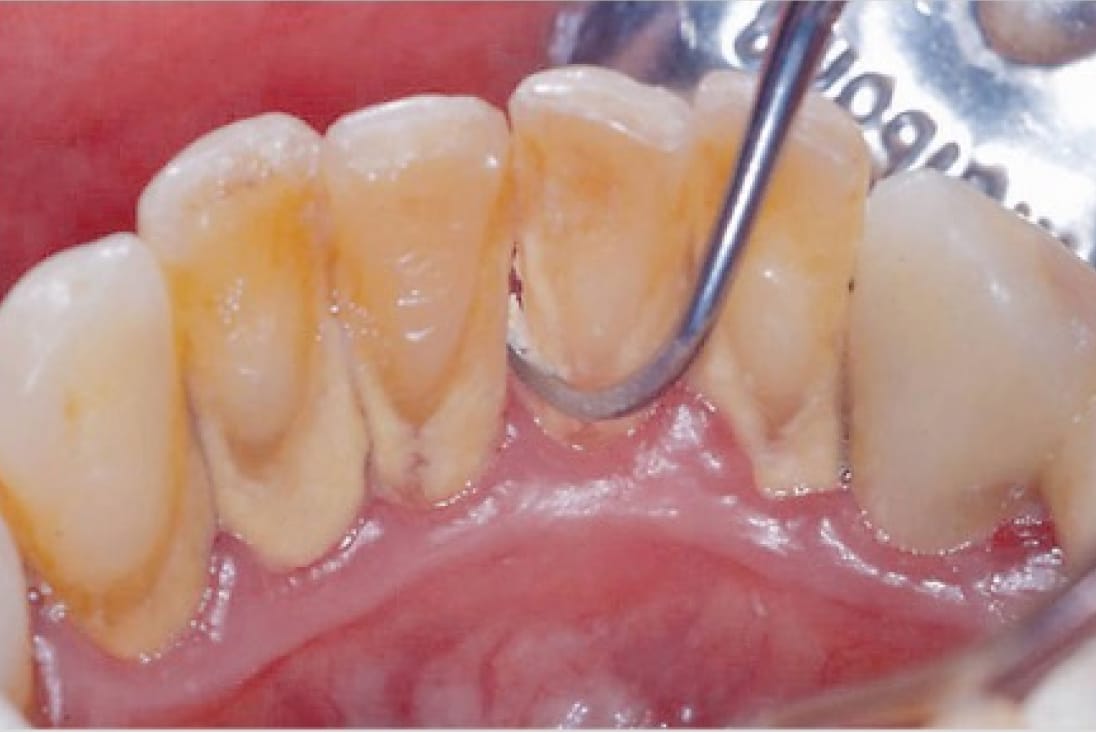

②2つのスケーラーを駆使した歯石除去

歯周病予防・改善のため、スケーラーという専門器具を用いて歯面や歯間に付着した歯石を取り除きます。大井町フラミンゴ歯科では「超音波スケーラー」と「ハンドスケーラー」の2つを駆使して、隅々まで徹底した処置を行なっています。

ハンドスケーラー

ハンドスケーラーは、歯の間や細かい部分に付着した歯垢・歯石の除去に適しています。超音波スケーラーと併用することで、取りこぼしのない徹底した歯石の除去が可能となります。

マイクロスコープを用いての精密な歯石除去

肉眼の最大80倍まで視野を拡大し、歯間や歯周ポケット内を目でしっかりと確認することにより、取りこぼしのない的確な処置が可能となります。